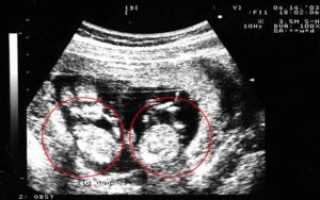

- Ультразвуковое исследование — самый достоверный способ увидеть и определить, какая у женщины беременность, более точный срок беременности, размеры плодов и все патологии, существующие у двоих эмбрионов (если таковые имеются). А также при помощи данного метода возможно определить однояйцевая или разнояйцевая беременность наблюдается у женщины.

Двойню на УЗИ можно увидеть и определить уже на 4-5 неделе беременности. Как правило, однояйцевые близнецы определяются позже, чем разнояйцевые (не раньше 12 недели).

Считается, что точно увидеть несколько эмбрионов, можно только при помощи УЗИ. На каком сроке определяют многоплодную беременность? Специалист может увидеть данный факт в 5-6 недель. Но, как правило, ее диагностируют во время первого скрининга в 12 недель.